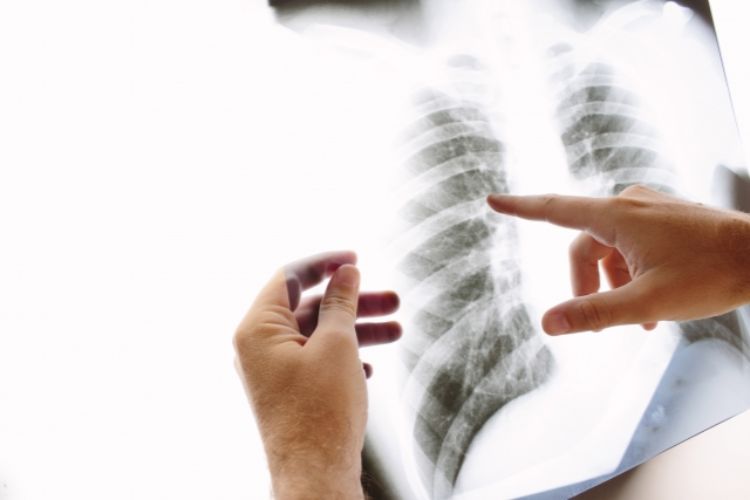

しかし検診さえ受けていれば絶対に安心であるとは言いきれない。実際、東京・杉並区の肺がん検診を受けていた40代女性のがんが2014年、2015年と複数年にわたって見逃され、2018年6月に死亡するという痛ましい事件も起きている。

受けなければ病気は見つからないが、受けても見落とされたり、そもそも意味のない検診だったりすることもあるうえ、多くの種類の検診を受ければそれだけお金もかかる。私たちはどう取捨選択すべきなのか。